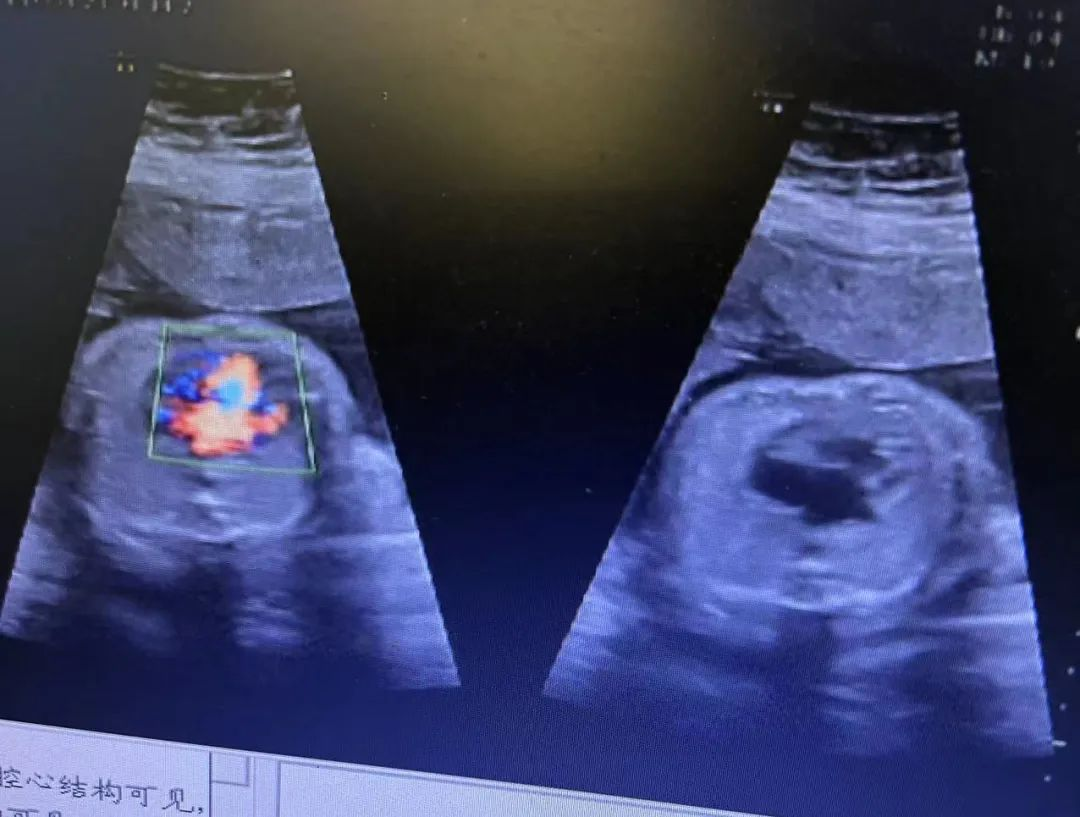

“單絨單羊”雙胞胎發(fā)生率僅為十萬(wàn)分之四,屬極其罕見(jiàn)又極其高危的雙胎妊娠。近日,武漢仁愛(ài)醫(yī)院超聲科就精準(zhǔn)為一位孕8周+的孕媽查出了“單絨毛膜單羊膜囊(MCMA)聯(lián)體雙胎”。